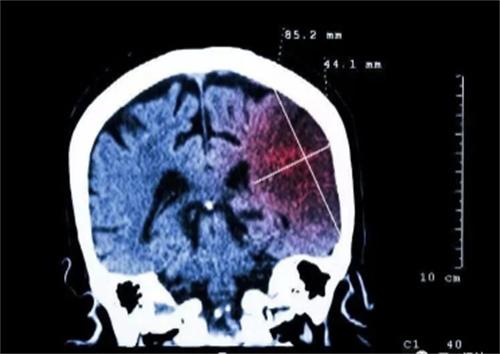

在近幾年發生腦梗塞的患者越來越多,而且逐漸向著年輕化的趨勢發展,腦梗和生活中很常見的一些不良習慣有著直接的關聯性,除了不良的生活會引起腦梗,部分腦梗竟然是吃出來的,在廚房中三種調料的濫用就是發生腦梗的幫兇,這三種材料暗藏危機,經常喜歡吃高鹽、高油、高糖的人群,有很大的幾率會患高血壓和腦梗。

經常吃高油食物,會使人的血液中含有的甘油三酯增多,血液變稠,逐漸形成斑塊沉積在血管壁上,時間長了就會發生腦梗,長期攝入高糖的飲食,會使人出現脂肪肝,體內糖分過多人體的肝臟就會釋放大量的血脂,從而形成高脂血癥,大大增加腦梗的風險。

長期攝入高鹽的食物會引發腦血栓的風險,很多上了年齡的老人,經常喜歡吃腌制的蔬菜,肉菜等食物,這些食物中含有大量的亞硝酸鹽,有致癌風險,同時也可以增加人患腦梗的幾率,很容易使腦梗復發,所以在日常生活中攝入這三大調料的時候,一定要注意用量,只要合理的飲食,能夠從一定程度上預防腦梗塞的發生,除了這三大調料的攝入量要注意,平時盡量減少酒精的攝入。